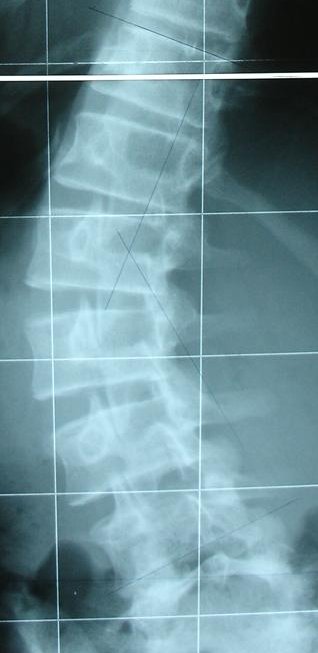

Die Ausschnitte sind im Anhang dabei. :)

ohne Korsett

ohneK.jpg (26.27 KiB) 11246 mal betrachtet

mit Korsett

mitK.jpg (16.28 KiB) 11246 mal betrachtet